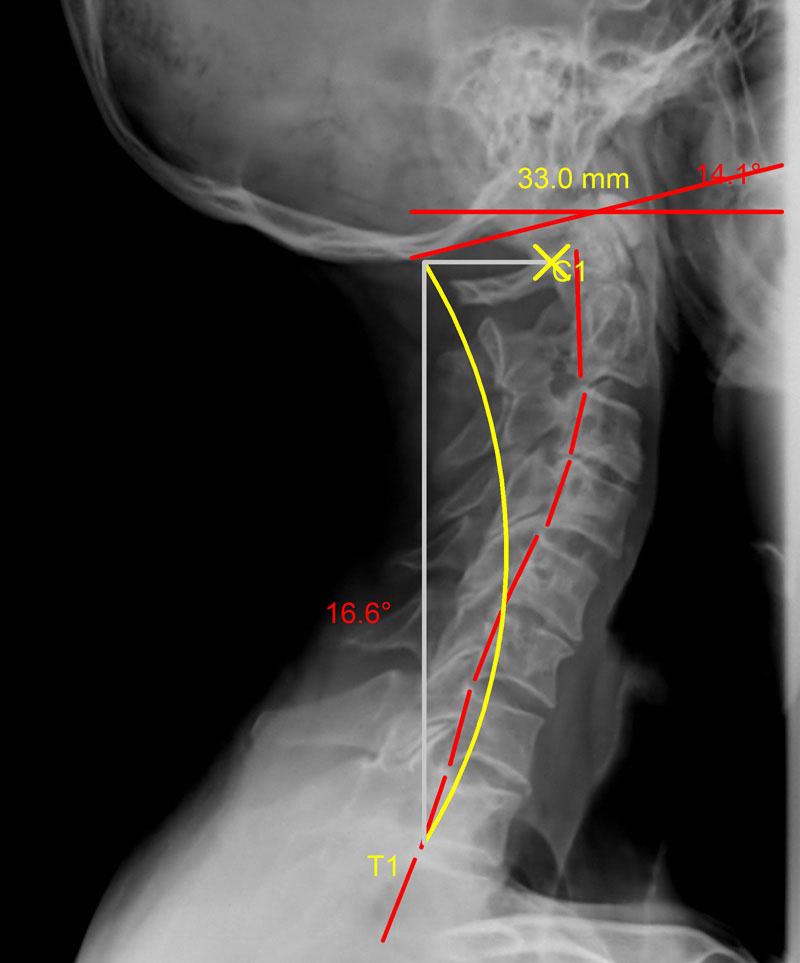

La ligne verte représente la courbure idéale et la rouge celle que forme la colonne vertébrale du patient vue de profil.